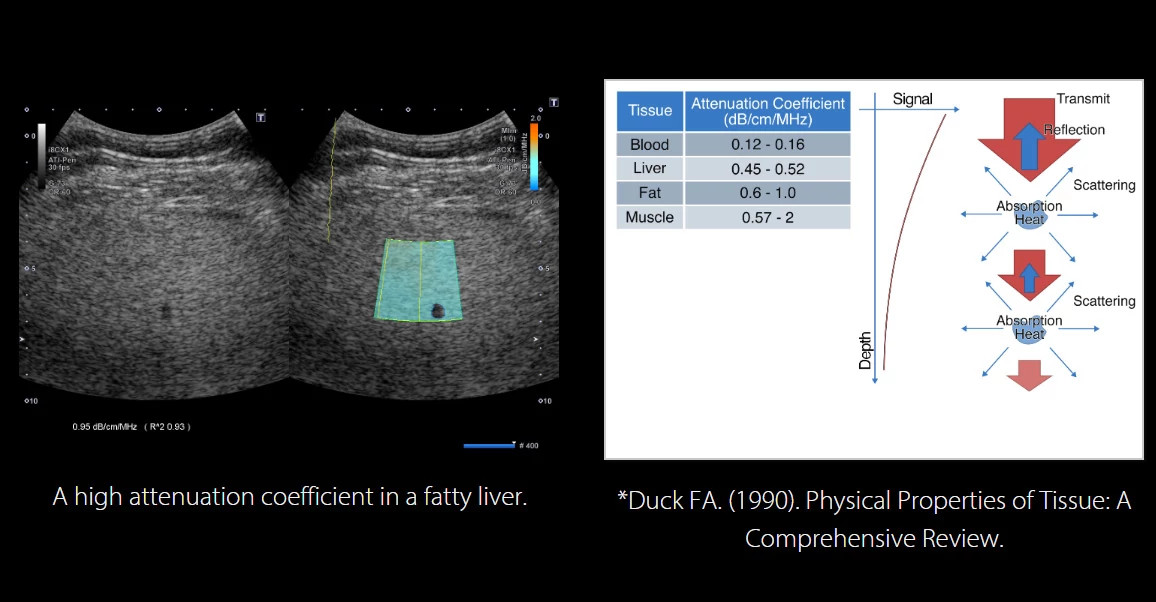

Attenuation Imaging (ATI) - A májösszetétel (pl. zsírtartalom) kvantifikálása és színkódolása

Az ATI a vizsgált régióban (ROI) mérhető ultrahang-csillapítás statisztikai elemzésével értékeli a szövet zsírtartalmát.

A rendszer képes a mintavétel pontosságát és homogenitását is kvantifikálni, ami alapvető fontosságú a megbízhatóság szempontjából.

Az ultrahanghullám szöveten való áthaladása során szóródás, abszorpció és hőtermelés következtében csillapodik. A csillapítás mértéke arányos a frekvenciával.

Az ATI technológia így objektív és reprodukálható módon segíti a zsírfelhalmozódás (steatosis) értékelését.